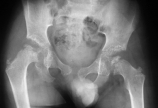

学生:10岁男孩,发现行走时步态异常3年,走长路后易疲劳。拍骨盆片显示双侧髋关节异常,体格检查髋关节活动无明显受限,是双侧Perthes病吗?  老师:不是双侧Perthes病,考虑多发性骨骺发育不良(multiple epiphyseal dysplasia,MED)。MED最初由Thomas Fairbank于1935年描述多发骨骺“不规则骨化”,并在1947年命名为dysplasia epiphysealis multiplex,是骨软骨发育不良的一个类型。一般是常染色体显性遗传,隐性遗传少见。文献报告发病率9-16/10万。  学生:MED有明确的病因吗?  老师:目前尚未完全明确。研究认为多个基因的突变可导致发病,COMP(聚基质蛋白)的突变是其中最常见的。编码相应蛋白的基因发生突变后,骨骺和骺板不规则,缺少骨样组织,软骨细胞排列不规则,骨小梁紊乱,多数骨骺异常骨化。  学生:一般临床表现怎么样?  老师:典型的MED病例,一般出生时无明显异常,以后逐渐出现症状。走路较晚,步态不稳,可伴有下肢畸形(髋内翻,膝内、外翻或踝外翻,马蹄内翻足),易疲劳,可早发髋、膝关节疼痛,可伴脊柱畸形(侧弯或后凸)。有时可伴有肩、肘异常,表现为肩外展受限及肘屈曲挛缩。多数身材矮小,但面部、头颅正常,智力发育正常。  学生:影像学上如何诊断?  老师:典型的MED影像学表现为多发骨骺出现迟缓,呈斑点状、扁平或分裂,密度增加。股骨颈干角减小,呈髋内翻。胫骨近端改变,引起胫内翻。椎体出现楔形变。桡、尺、腕、掌、跖骨等均可发生相应的骨骺变化。随年龄增长,骨骺的改变逐步消失,但扁平畸形仍存在。严重者可继发退行性骨关节病。成人以后骨骺骨化,影像学表现不典型。  学生:需要与哪些疾病进行鉴别诊断?  老师:临床上需要鉴别的常见疾病包括双侧Perthes病、软骨发育不全、髋关节感染等。Perthes病少见双侧受累,晚期会继发髋臼发育不良,而非髋臼软骨形态异常,且常伴干骺端无囊性变;典型软骨发育不全(Achondroplasia)股骨近端、肱骨近端可呈“舌样”改变,髋臼可呈“三角形”;关节结核、类风湿类疾病多呈破坏性改变,会导致关节间隙减小,而MED早期多无此类改变,晚期随着年龄可出现早发OA改变。  学生:MED治疗的指征?  老师:治疗包括药物治疗和手术治疗。早期主要为对症药物治疗,药物治疗目的主要是缓解疼痛、延缓受累关节的破坏及推迟骨性关节炎的发生时间。必要时可转诊至风湿病学医生或疼痛科医生。控制体重对MED病人意义较大,同时,在指导进行康复治疗时,避免对受累关节的保护。  手术治疗目的包括缓解疼痛、矫正成角畸形或关节挛缩,对晚期骨性关节炎可能需要行关节置换术。对儿童期出现髋关节疼痛或伴有半脱位病人,可行造盖(shelf)或内移截骨术改善覆盖,不宜行股骨近端内翻截骨术,以免加重髋内翻的程度。曾有学者试行关节镜手术行关节清理,但有人质疑此类手术可能会加速早发OA。  学生:下肢畸形如何矫正?  老师:可以拍双下肢站立位全长片分析下肢机械轴线。对小年龄MED患儿的下肢成角畸形,可以行半骺阻滞术,利用“生长引导”达到逐渐矫正的效果,但是,由于这类孩子常身材相对矮小,生长潜力相对小,应用半骺阻滞技术时存在矫形时间长、效果不佳、并发症发生率相对高可能。对接近骨骼发育成熟儿童可以行截骨矫形术尽可能重建下肢机械轴线。参考资料:1.Medscape2.Salem Bajuifer, Merv Letts. Multiple epiphyseal dysplasia in children:Beware of overtreatment! Can J Surg, Vol. 48, No. 2, April 20053.Sheila Unger. Multiple epiphyseal dysplasia: clinicaland radiographic features, differentialdiagnosis and molecular basis. Best Practice & Research Clinical Rheumatology. Vol. 22, No. 1, pp. 19–32, 20084.D Ballhausen. Recessive multiple epiphyseal dysplasia (rMED):phenotype delineation in eighteen homozygotes forDTDST mutation R279W. J Med Genet 2003;40:65–71